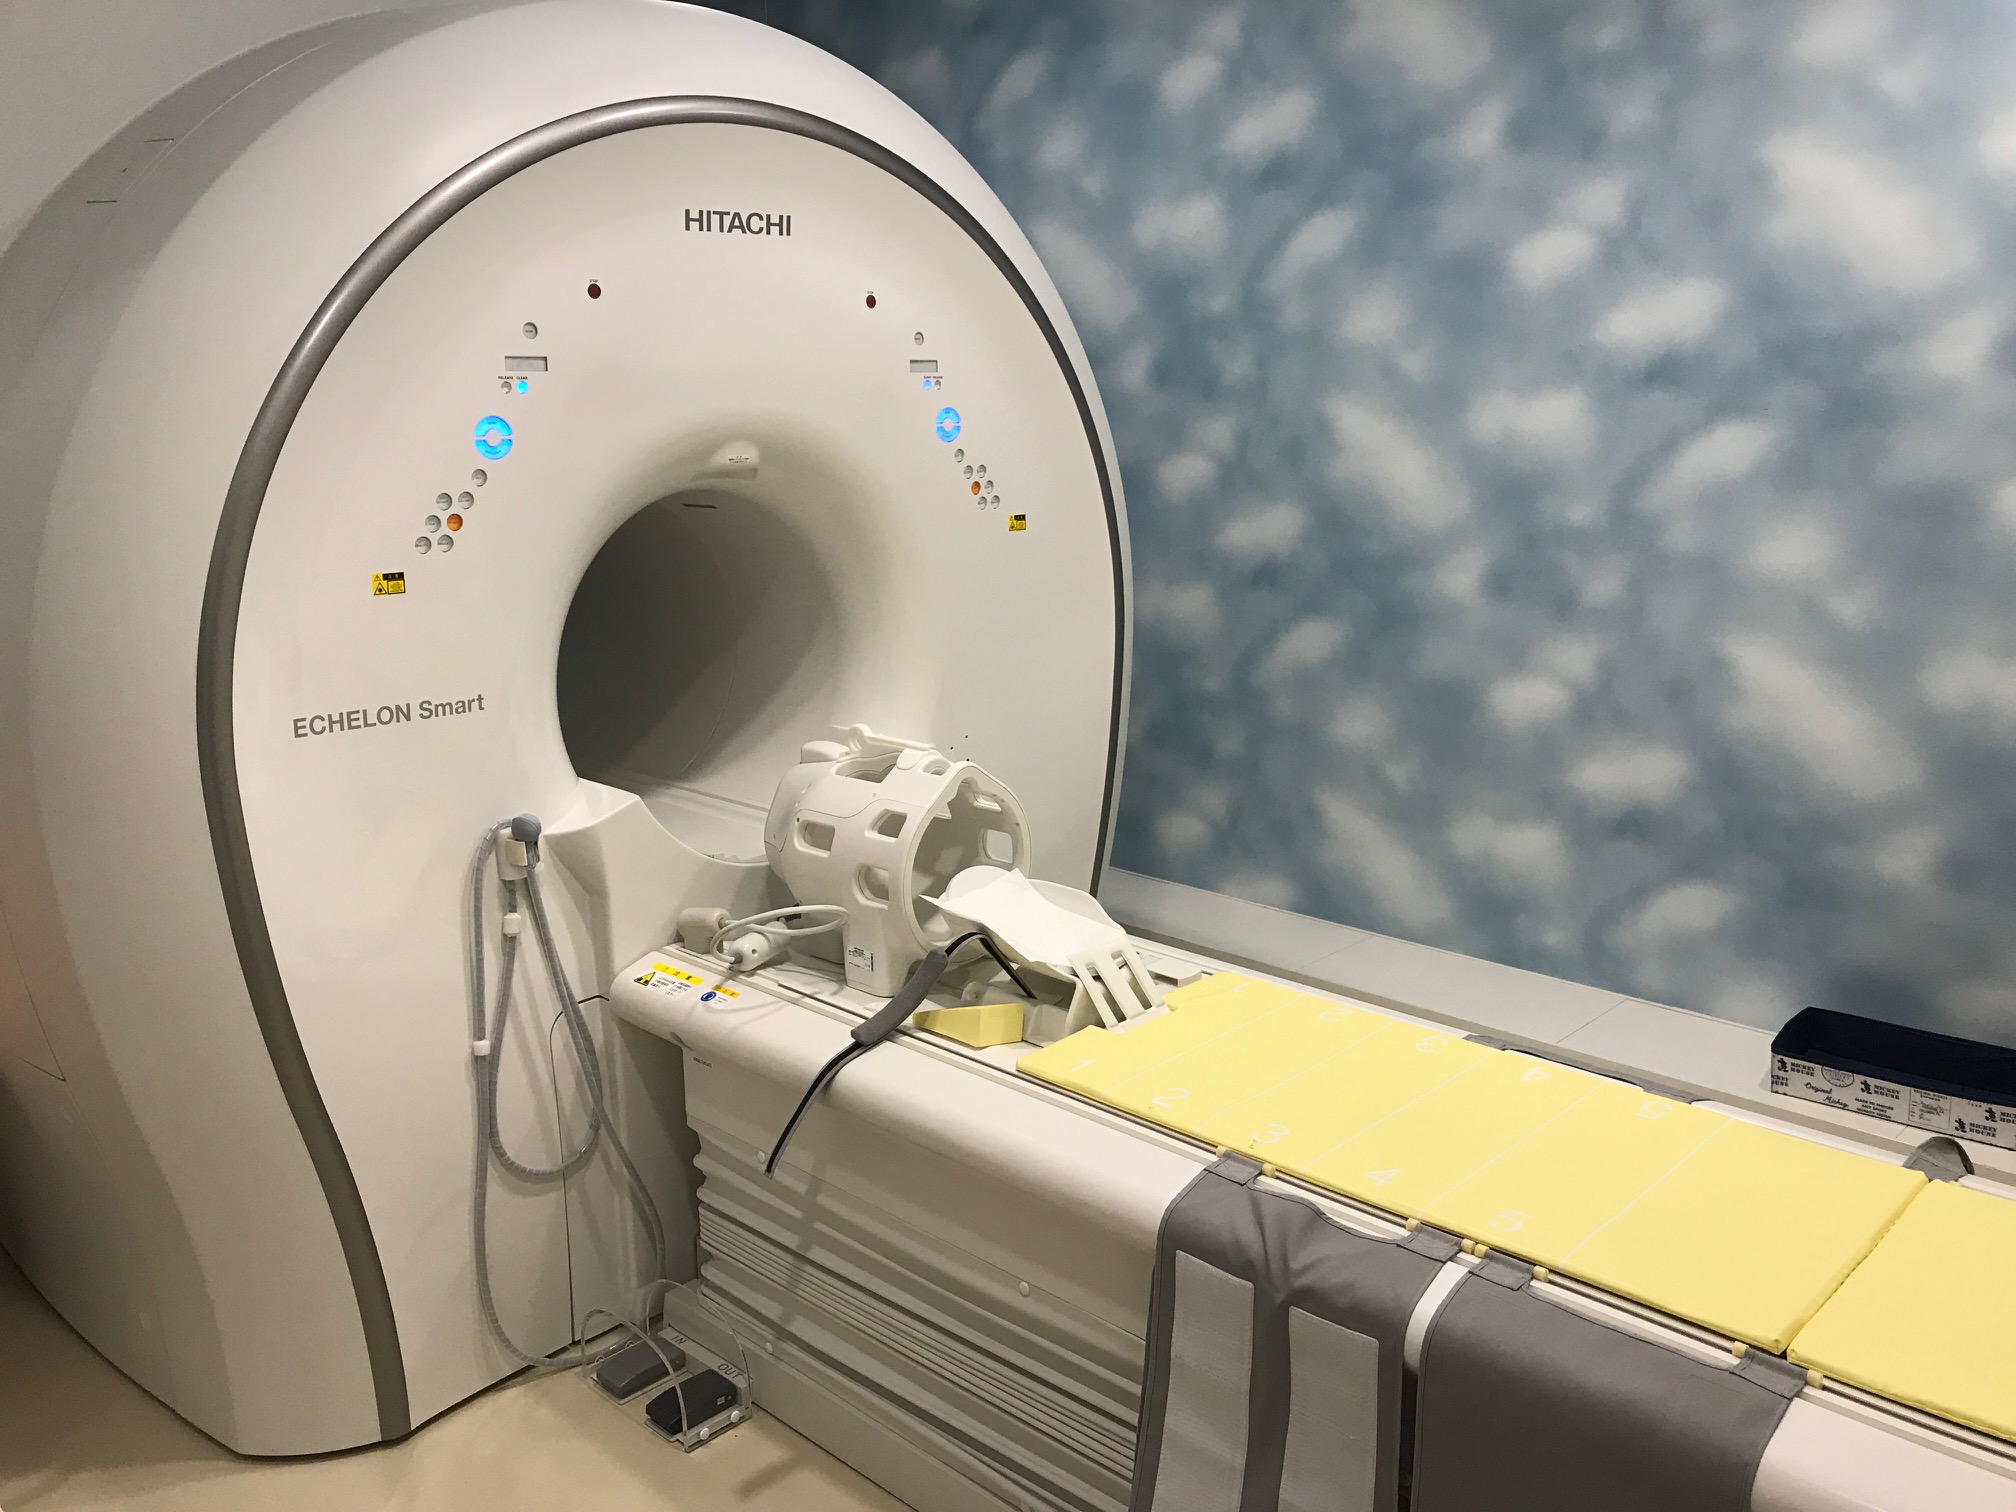

MRI(日立製作所 ECHELON Smart / 超伝導1.5T)

頭部だけでなく、脊椎、関節など全身の撮影が可能です。従来のMRIと比較し高画質で、撮影時間も20分程度と短くなっています。

MRI装置(日立製作所 ECHELON Smart / 超伝導1.5T)